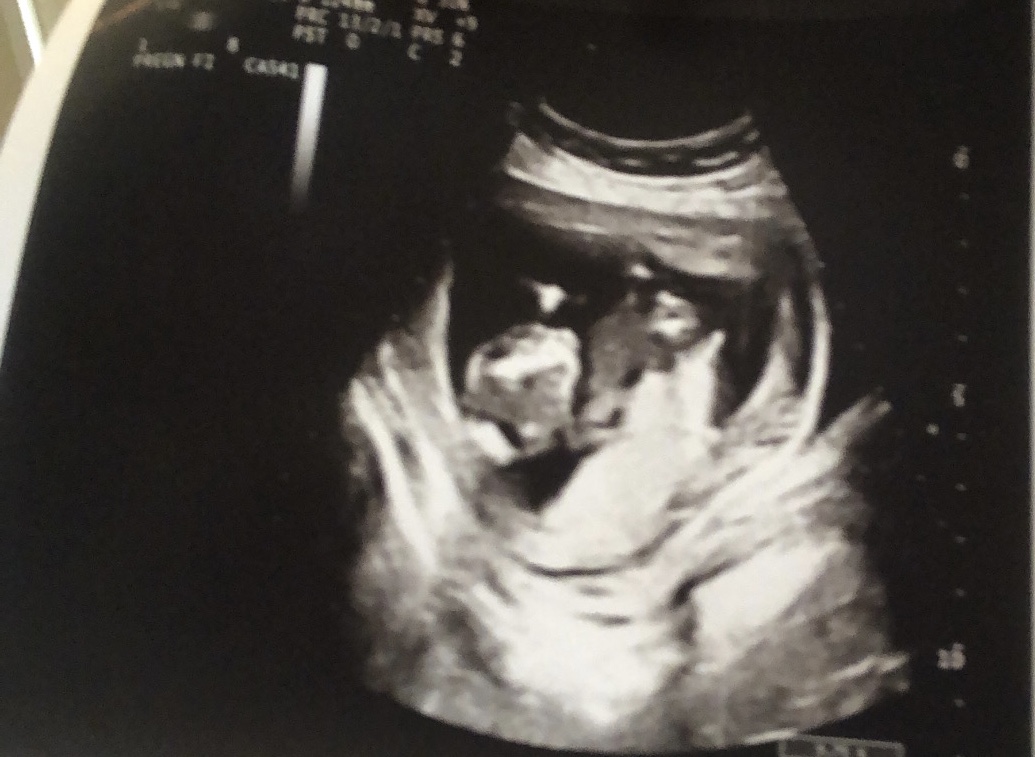

Dünkü ultrasonumuz solda duruyor bacakları kapalıydı doktor kesinlikle emin değilim ama tahminim erkek dedi

• 9D92E104-1E90-464A-848C-3A961F334D95.jpeg

9D92E104-1E90-464A-848C-3A961F334D95.jpeg

200 KB · Görüntüleme: 74